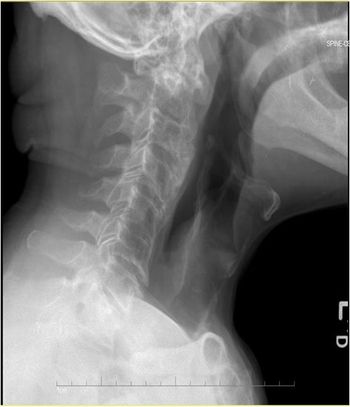

The elderly man with hypertension and polyarticular tophaceous gout experiences intermittent dizziness, neck pain, and arm weakness. Which condition is responsible?

An 82-year-old man with hypertension and gout developed periods of dizziness, neck pain, and arm weakness. Could the gout be responsible?